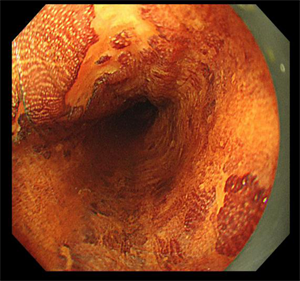

5月14日,80岁的李大爷(化名)因“再发胸闷气喘加重10天”在我院心内科住院期间,经检查,胃镜显示该患者为食管距门齿25~35cm可见两处1.5*2.0cm发红不规则糜烂,病理活检显示为鳞状上皮呈高级别上皮内瘤变(高级别上皮内瘤变相当于原位癌,也称之为食管早癌)。由于该患者曾多次因”慢阻肺、心脏瓣膜病、心功能不全、慢性房颤”住院治疗,且已有80岁高龄,若进行食管癌手术切除治疗风险大、预后生活质量会明显下降。消化内科吴斌及团队根据老人的实际情况反复研究,决定为李大爷行食管早癌消化内镜下黏膜剥离术。

是通过内镜前端针对粘膜、病灶周围进行注射,在胃镜下对病变粘膜进行切割剥离,通过剥离使病灶离开胃壁或者是粘膜层。ESD术具有创伤小、不改变消化道结构、避免外科手术风险、提高术后生活质量等优点,可以帮助早期肿瘤病人达到治愈的目的。